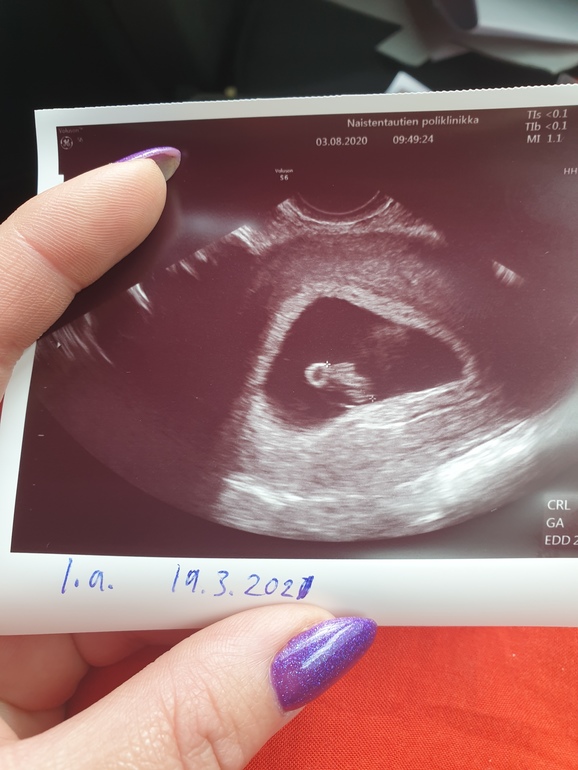

Первое узи

Я БЕРЕМЕННА !Итак прошла я уже приличную часть квеста под названием ЭКО 😂 это и тесты с 1 ДПП, и ХГЧ, и 3 кровотечения. Сегодня наконец были на узи и мы в порядке, сердечко бьётся отлично ❤❤❤